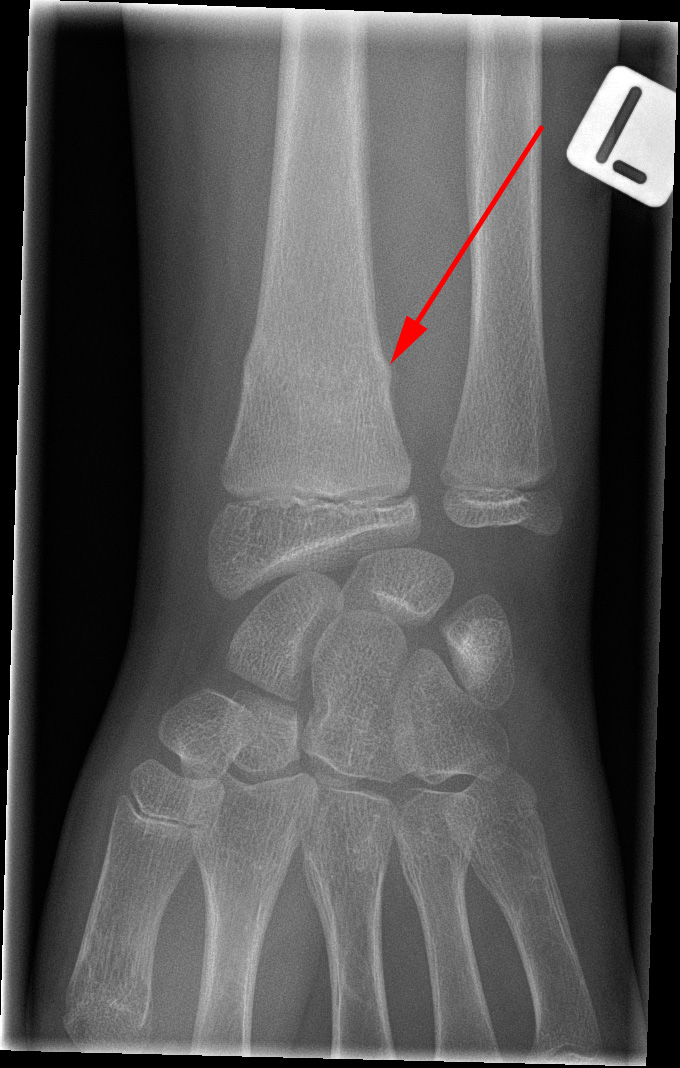

Røntgenundersøgelse af venstre hånd viser en såkaldt green-stick brud (rød pil) hos en yngre person.